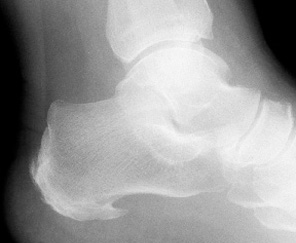

A heel spur is a focal point of bone growth on the heel. The bone growth usually extends forward towards the toes. Heel spurs are visible on X-ray. The spur is theorized to occur when the plantar fascia tissue attaching into the calcaneus (heel bone) tears away from the bone and injures the outer layer (periosteum) of the bone. Small amounts of bleeding may occur at this site and then this area can ossify and form a heel spur. It is not the spur that causes the pain, but the continued tension and tearing of tissue at this location.

X-ray examination often reveals an apparent fragmentation of the growth plate. Growth is not impaired by this condition. Treatment is similar to that for plantar fasciitis. Decrease activity. Initially a heel lift is used, which often fails to relieve the pain. Custom orthoses and gentle calf stretching is usually quite effective in treating this condition and allowing a reasonably rapid return to sports.